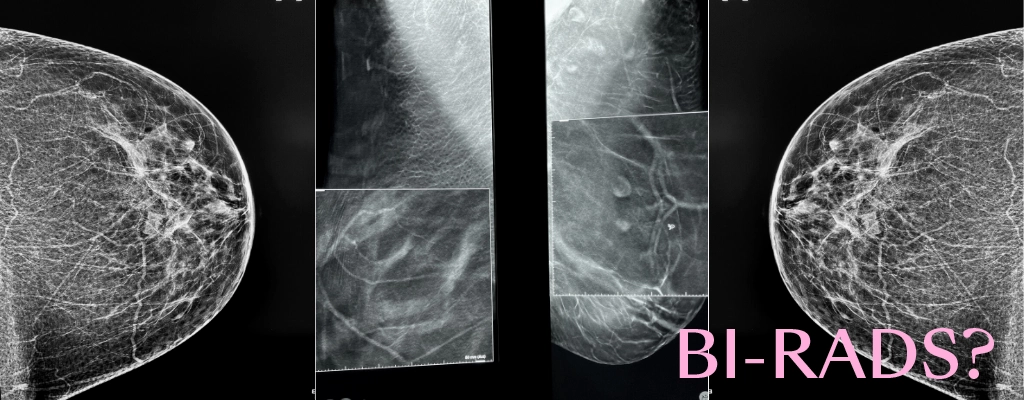

Există termeni specifici și coduri, cunoscute în lumea medicală drept „terminologie BIRADS”, care are rolul de a uniformiza și eficientiza felul în care medicii oferă acest rezultate în urma investigațiilor. Acest lucru înseamnă că și alți medici radiologi vor înțelege precis rezultatul care ți s-a dat, dar este la fel de important ca și tu să înțelegi ce înseamnă concluzia scrisă pe raport.

Codul BI-RADS (Breast Imaging – Reporting and Database System) a fost introdus de Colegiul American de Radiologie (ACR), ca o modalitate eficientă și uniformă de a raporta sănătatea sânilor, astfel încât orice medic de oriunde să înțeleagă gradul de risc al leziunilor descrise, făcând rezultatele să fie mai clare și să aibă un grad mai mare de acuratețe. Acesta este motivul pentru care i se mai spune și scor de risc.

Un control imagistic al sânilor, fie ca este vorba de o ecografie mamară, mamografie sau de un RMN mamar trebuie să se încheie cu un rezultat scris pe care sa apară în mod clar codul BI-RADS.

Acest cod indică gradul de risc detectat în urma examinării și este numerotat de la 0-6.

CE REPREZINTĂ FIECARE COD ÎN PARTE?